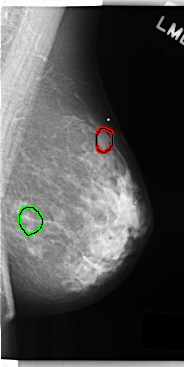

FILE: C_0247_1.LEFT_MLO.OVERLAY

TOTAL_ABNORMALITIES 2

ABNORMALITY 1

LESION_TYPE MASS SHAPE OVAL MARGINS CIRCUMSCRIBED

ASSESSMENT 3

SUBTLETY 5

PATHOLOGY BENIGN

TOTAL_OUTLINES 1

BOUNDARY

ABNORMALITY 2

LESION_TYPE CALCIFICATION TYPE AMORPHOUS DISTRIBUTION CLUSTERED

ASSESSMENT 4

SUBTLETY 3